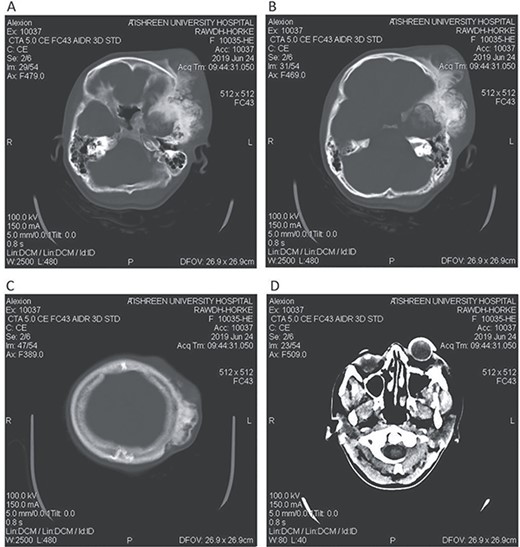

CT head tissue window. A, B. Invasion and destruction of the surrounding tissue. C. Minor shift of the elements of the midline to the right side due to the edema. D. The edema applies pressure to the left lateral ventricle.

A 17-year-old female presented with a history of osteosarcoma that was confirmed after undergoing a surgery to remove an enlarging bone tumor in the left temporal region 2 years ago. She later got pregnant and delivered her child but never got back for a checkup until she was admitted to our hospital with a severe and unresponsive to medication headache that progressed over the course of 6 months and blurred vision that progressed to complete left-sided vision loss. Physical examination revealed a tough and mobile yet fixed at the base 7-cm mass towards the left of the frontal bone. Many more masses were revealed in the left side of the skull including the anterior cranial fossa, orbit, base of the skull and the left part of the occipital region where the previous procedure was performed (Fig. 1). These masses had been increasing in size probably under the influence of pregnancy hormones causing pain that radiated along the orbital and maxillary branches of the left trigeminal nerve. Physical examination and past medical history were otherwise unremarkable. Laboratory tests were all normal, and her family history was negative. Staging studies showed no evidence of distant metastatic disease in the chest, the abdomen and the pelvis. CT scan of the skull revealed a bone-forming non-lytic lesion accompanied by periosteal reaction. This lesion bulges to the outside towards the scalp spreading into both the soft tissues and the inside of the entire left side of the skull with a sunburst-pattern (Figs 2 and 3). Its rims are unsymmetrical and pointy, and it bulges into the left orbit outside the muscles causing exophthalmos with a semi-complete proptosis of the eyeball out of the orbit (Figs 2 and 3). This lesion applies pressure to the left frontal and temporal lobes causing mild edema in both these lobes without invading the brain tissue. This edema in turn applies pressure to the left lateral ventricles (minor shift of the elements of the midline to the right side can be seen on CT) (Fig. 4). Due to the tumor’s wide spread, the surgical procedure was performed in two stages (approximately 6-hour-long each). In the first stage, the bone mass was removed through a procedure of wide skull approach including the frontal, temporal and parietal bones and a removal of the invading part of the temporal muscle. Moreover, the lateral wall and roof of the left orbit were removed, the left optic nerve was dissected free and part of the meninges was removed and replaced with an autogenic patch from the fascia lata. Then, the bone loss was compensated for by using bone cement Synicem VTP (poly methyl methacrylate and Barium sulfate), and the orbit was rebuilt; the eyeball was placed back with noticeable decline of the exophthalmos. In the second stage, a complementary left parietal occipital incision of the previous approach was performed 3 weeks later; the remaining of the frontal and occipital bones was removed, and a partial mastoid surgery was done. Furthermore, the cavernous sinus were revealed and found to be not invaded. Later on, the normal skull shape was restored using the same cement. The histopathology of the lesion revealed proliferation of neoplastic chondroblasts, osteoblasts and spindle-shaped cells. The features are consistent with low-grade chondroblastic osteosarcoma (Fig. 5). The patient did not need ICU admission. She recovered well 3 days after the surgery and was discharged with no deficits. A CT scan that was performed post-operatively revealed that the masses were successfully excised (Figs 6 and 7). At the last follow-up 1 month post-operation, the patient was scheduled to undergo a course of radiotherapy, 60 Gy of radiotherapy in 30 fractions over 4 weeks without chemotherapy, as it is not recommended with low-grade osteosarcoma.